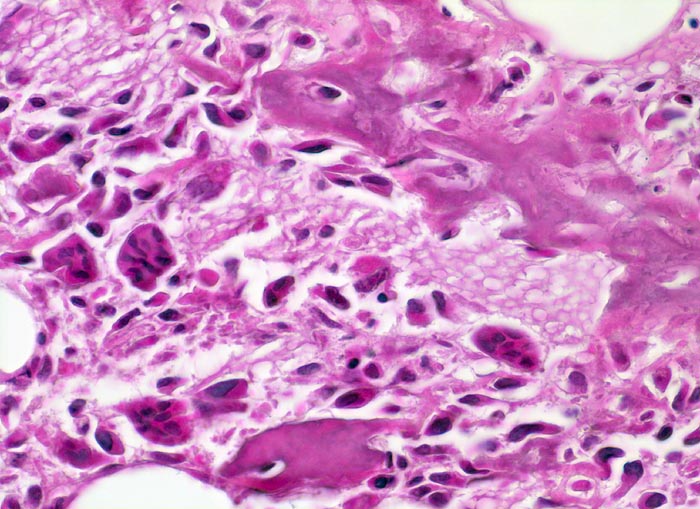

Osteosarkom

Atypische spindelige Tumorzellen mit hyperchromatischen Kernen bilden fein verzweigtes schmales verkalktes Osteoid. Tumorzellen liegen teils mitten im Osteoid gefangen. Neben den Tumorzellen mehrkernige reaktive osteoklastäre Riesenzellen.

16 jähriger Jugendlicher mit seit mehreren Wochen bestehenden belastungsunabhängigen Schmerzen im distalen Femur rechts oberhalb des Knies (Metaphyse). Im Röntgenbild irreguläre Verdichtung, zum Teil auch Aufhellung der ursprünglichen Knochenstruktur mit Zerstörung der Corticalis und spiculaartige (=sonnenstrahlenähnliche) Periostreaktion. Im Serum erhöhte alkalische Phosphatase.

Histologie

400